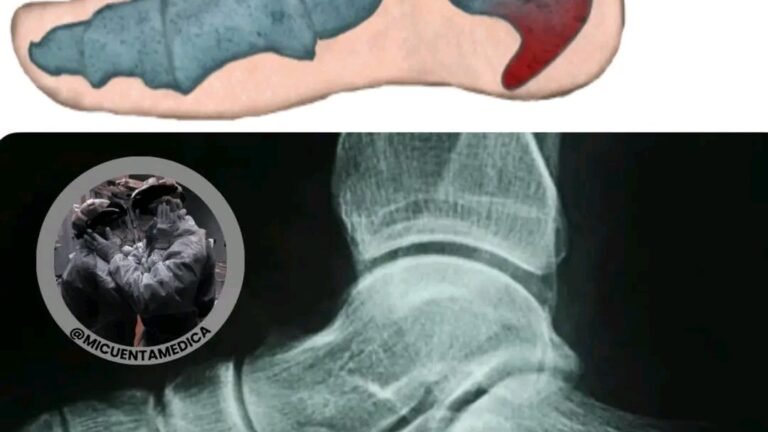

There are pains that seem small, until you take the first step of the day…